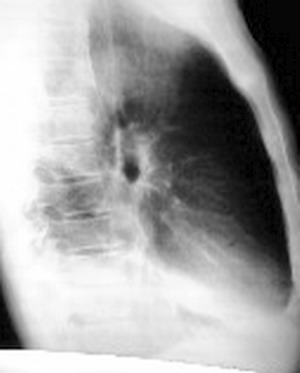

标题: CT6943:[讨论]胸部,M/67Y,体检发现。

ct值约12hu。

ct值约12hu

右肺下叶支气管阻塞,右下叶不张,考虑中心型肺癌伴下叶不张

右肺下叶支气管闭塞,中间段支气管狭窄,下叶不张,胸腔及叶间积液.中心型肺癌伴下叶肺不张.胸腔和叶间积液.

右肺下野后部均匀低密度影,边缘锐利,前缘外突(不支持肺不张),纵隔内未见明显肿大淋巴结,右下肺门结构显示欠清,临床资料太过简单,考虑右侧后胸部包裹性积液。其他待排。建议密切结合临床其他检查。